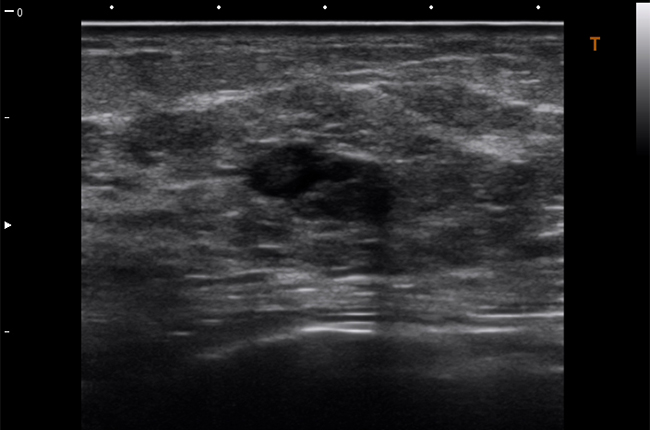

Якщо Вам потрібна висока якість діагностики завжди і всюди, Viamo c100 — це ідеальне рішення. Система Viamo c100 поєднує в собі всі переваги переносної ультразвукової системи та діагностичну точність, ефективність і зручність, які притаманні стаціонарним апаратам.

Viamo c100 – сканер, розроблений для ситуацій, де мобільність – необхідний чинник, а якість зображення має вирішальне значення. Апарат належить до експертного класу та підтримує технології візуалізації останнього покоління, що дозволяє отримати зображення неперевершеної якості – основний чинник успішної діагностики в ургентних ситуаціях.

Поверхневі органи та малі структури

Сонна артерія

Скелетно-м'язова система